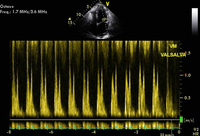

Técnica de Valsalva confirmando relaxamento comprometido

Do acervo do Dr. Marc Del Rosario